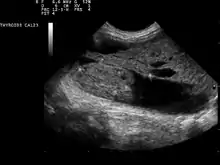

Обычно пальпаторно выявляются узлы, размеры которых превышают 1 см. С помощью датчика (частота 7,5 МГц) проводится эхоскопия (ультразвуковое исследование щитовидной железы). Метод существенно расширяет возможности практикующих врачей на этапе диагностического поиска — позволяет не только выявить дополнительное образование в щитовидной железе, но и установить основные признаки узла: характер роста, наличие капсулы, кальцинатов, фиброза, жидкости или коллоида внутри узла.

Заболевание чаще развивается у женщин в возрасте 50—60 лет, длительно проживающих в условиях природного дефицита йода и страдающих многоузловым эутиреоидным зобом. Причины возникновения заболевания полностью не изучены. Клиническая симптоматика при многоузловом токсическом зобе аналогична симптоматике вышеизложенных заболеваний, протекающих с синдромом тиреотоксикоза. Отсутствуют офтальмопатия и претибиальная микседема. При физикальном исследовании определяется несколько узлов, как правило, округлой формы, образующих единый конгломерат или не связанных между собой, с гладкой поверхностью, четкими контурами, смещаемых при глотании с щитовидной железой. Ультразвуковая картина соответствует данным физикального исследования. Иногда при помощи УЗИ выявляются дополнительные непальпируе- мые узлы. Контуры узлов четкие, структура однородная, эхогенность, как правило, выше по сравнению с экстранодулярной тканью щитовидной железы. На основании радионуклидного сканирования выделяют три формы многоузлового поражения щитовидной железы, протекающих с синдромом тиреотоксикоза: многоузловой зоб с гиперфункционирующими узлами и нефункционирующей экстранодулярной паренхимой (60—80 %); многоузловой зоб с нефункционирующими узлами и гиперфункционирующей экстранодулярной паренхимой (10—20 %); многоузловой зоб, при котором одновременно гиперфункционируют и узлы, и экстранодулярная паренхима (3-5 %). Для исключения рака щитовидной железы необходимо производить тонкоигольную аспирационную биопсию и цитологическое исследование. С этой целью пунктируют каждый узел и экстранодулярную паренхиму обеих долей щитовидной железы.